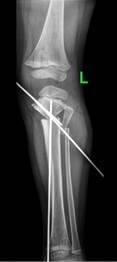

Болезнь Блаунта Фото 115 фотографий